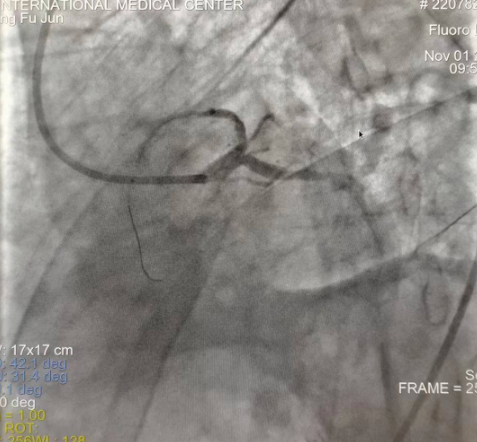

閉塞的血管再通時間取決于急救時長、轉(zhuǎn)運時長和治療時長,在前兩方面,醫(yī)院已為患者爭取了最短時間。患者家屬遠在陜北,雖然已在趕來的路上,但最快抵達西安也要3小時,在與患者家屬電話溝通同意急診手術(shù)后,醫(yī)療總值班代家屬簽字,康曉軍在請示心臟病醫(yī)院王海昌院長及心臟內(nèi)科CCU尚福軍主任后,積極進行術(shù)前準備。在沒有家屬陪同、沒有交費、沒有辦入院手續(xù)的情況下,患者經(jīng)胸痛中心綠色通道被送往心臟冠脈介入手術(shù)室,打通了完全閉塞的心臟前降支近段血管。